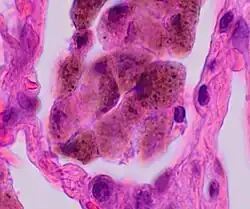

It is a histological finding, not a pathological description. When associated with disease, it is known as "Respiratory bronchiolitis-associated interstitial lung disease" or "RB-ILD".[4] Also, this disease is predominantly found in the upper lobe with centrilobar ground glass nodules. Importantly, no fibrosis is involved, just bronchial wall thickening. Treatment is to stop smoking.

The appearance is similar to desquamative interstitial pneumonia, and some have suggested that the two conditions are caused by the same processes.[5]